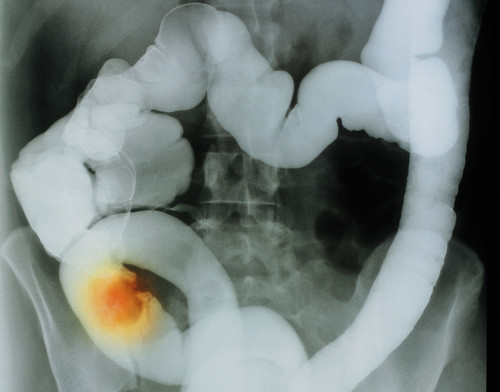

14 358 personer som var blitt behandlet for kreft før fylte 21 år ved 26 sykehus i USA og Canada, ble kontaktet minst fem år etter at den første kreftdiagnosen ble stilt (median 22,3 år) (1). 45 hadde utviklet gastrointestinal cancer, mot forventet ni (standardisert insidensratio (SIR) = 4,6; 95 % KI 3,4 – 6,1).

Risikoen var høyest hos dem som hadde hatt Hodgkins lymfom eller Wilms tumor eller var blitt behandlet med abdominal røntgenterapi, procarbazine i høye doser eller platinaholdige legemidler. Forfatterne anbefaler tidligere screening for tykktarmskreft for dem som har overlevd kreft i barneårene enn det som anbefales for normalbefolkingen.